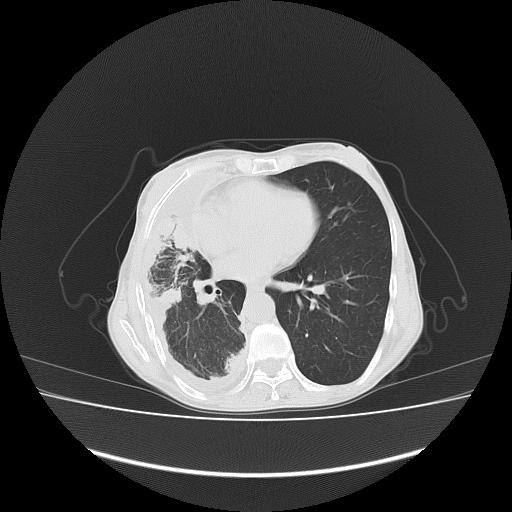

标题: CT16930:女 59 胸痛6个月 胸水脱落细胞学见瘤细胞 [打印本页]

标题: CT16930:女 59 胸痛6个月 胸水脱落细胞学见瘤细胞

可见多发肺内病灶,且胸膜病灶较多有圆球状而非丘状,多考虑胸膜转移瘤伴胸腔积液,右侧胸廓缩小固定,且部分病灶呈丘状,尚不除外恶性胸膜间皮瘤伴肺内转移

恶性胸膜间皮瘤伴肺内转移可能性大;或胸膜、肺内均为转移瘤,左肺下叶亦见多发小结节影。

右侧胸廓塌陷,右侧胸膜广泛增厚并见多发胸膜结节,右侧少量胸腔积液并包裹。

右侧胸膜转移瘤,原发灶可能就在在右肺,另外建议检查右侧乳腺.

右胸腔结节均考虑来自胸膜(部分来源于叶裂),考虑胸膜间皮瘤或转移瘤.